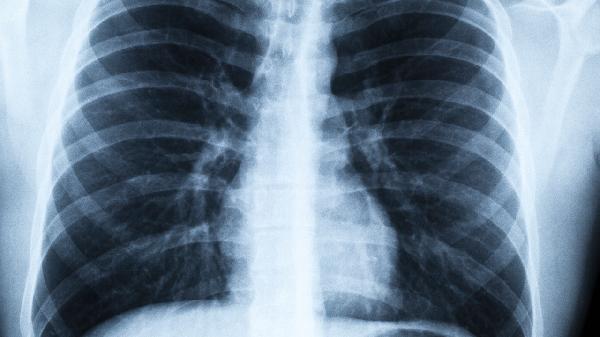

肺結(jié)節(jié)通常是指肺部直徑≤3cm的局灶性類圓形、密度增高的實性或亞實性肺部陰影,可分為良性結(jié)節(jié)和惡性結(jié)節(jié),如果為良性的結(jié)節(jié),且體積較小,單發(fā)和多發(fā)通常都不算危險,不會對身體造成嚴(yán)重的損傷,通過積極規(guī)范的治療后,一般預(yù)后良好。

如果肺結(jié)節(jié)的體積比較大,導(dǎo)致患者出現(xiàn)了明顯的不適癥狀,或者是惡性的肺結(jié)節(jié),無論是單發(fā)還是多發(fā),都比較危險,可能會使患者出現(xiàn)咳嗽、胸悶、氣短、咯血等現(xiàn)象,如果不及時治療,還可能會危及生命。

如果為良性的肺結(jié)節(jié),體積較小,且沒有引起不適癥狀,可以定期復(fù)查,先不予治療。如果體積較大,有明顯的不適癥狀,或者為惡性肺結(jié)節(jié),應(yīng)及時在醫(yī)生的操作下行肺葉切除術(shù)、肺楔形切除術(shù)等手術(shù)治療。治療后,做好護(hù)理工作,糾正不良的生活習(xí)慣,有利于促進(jìn)身體康復(fù)。